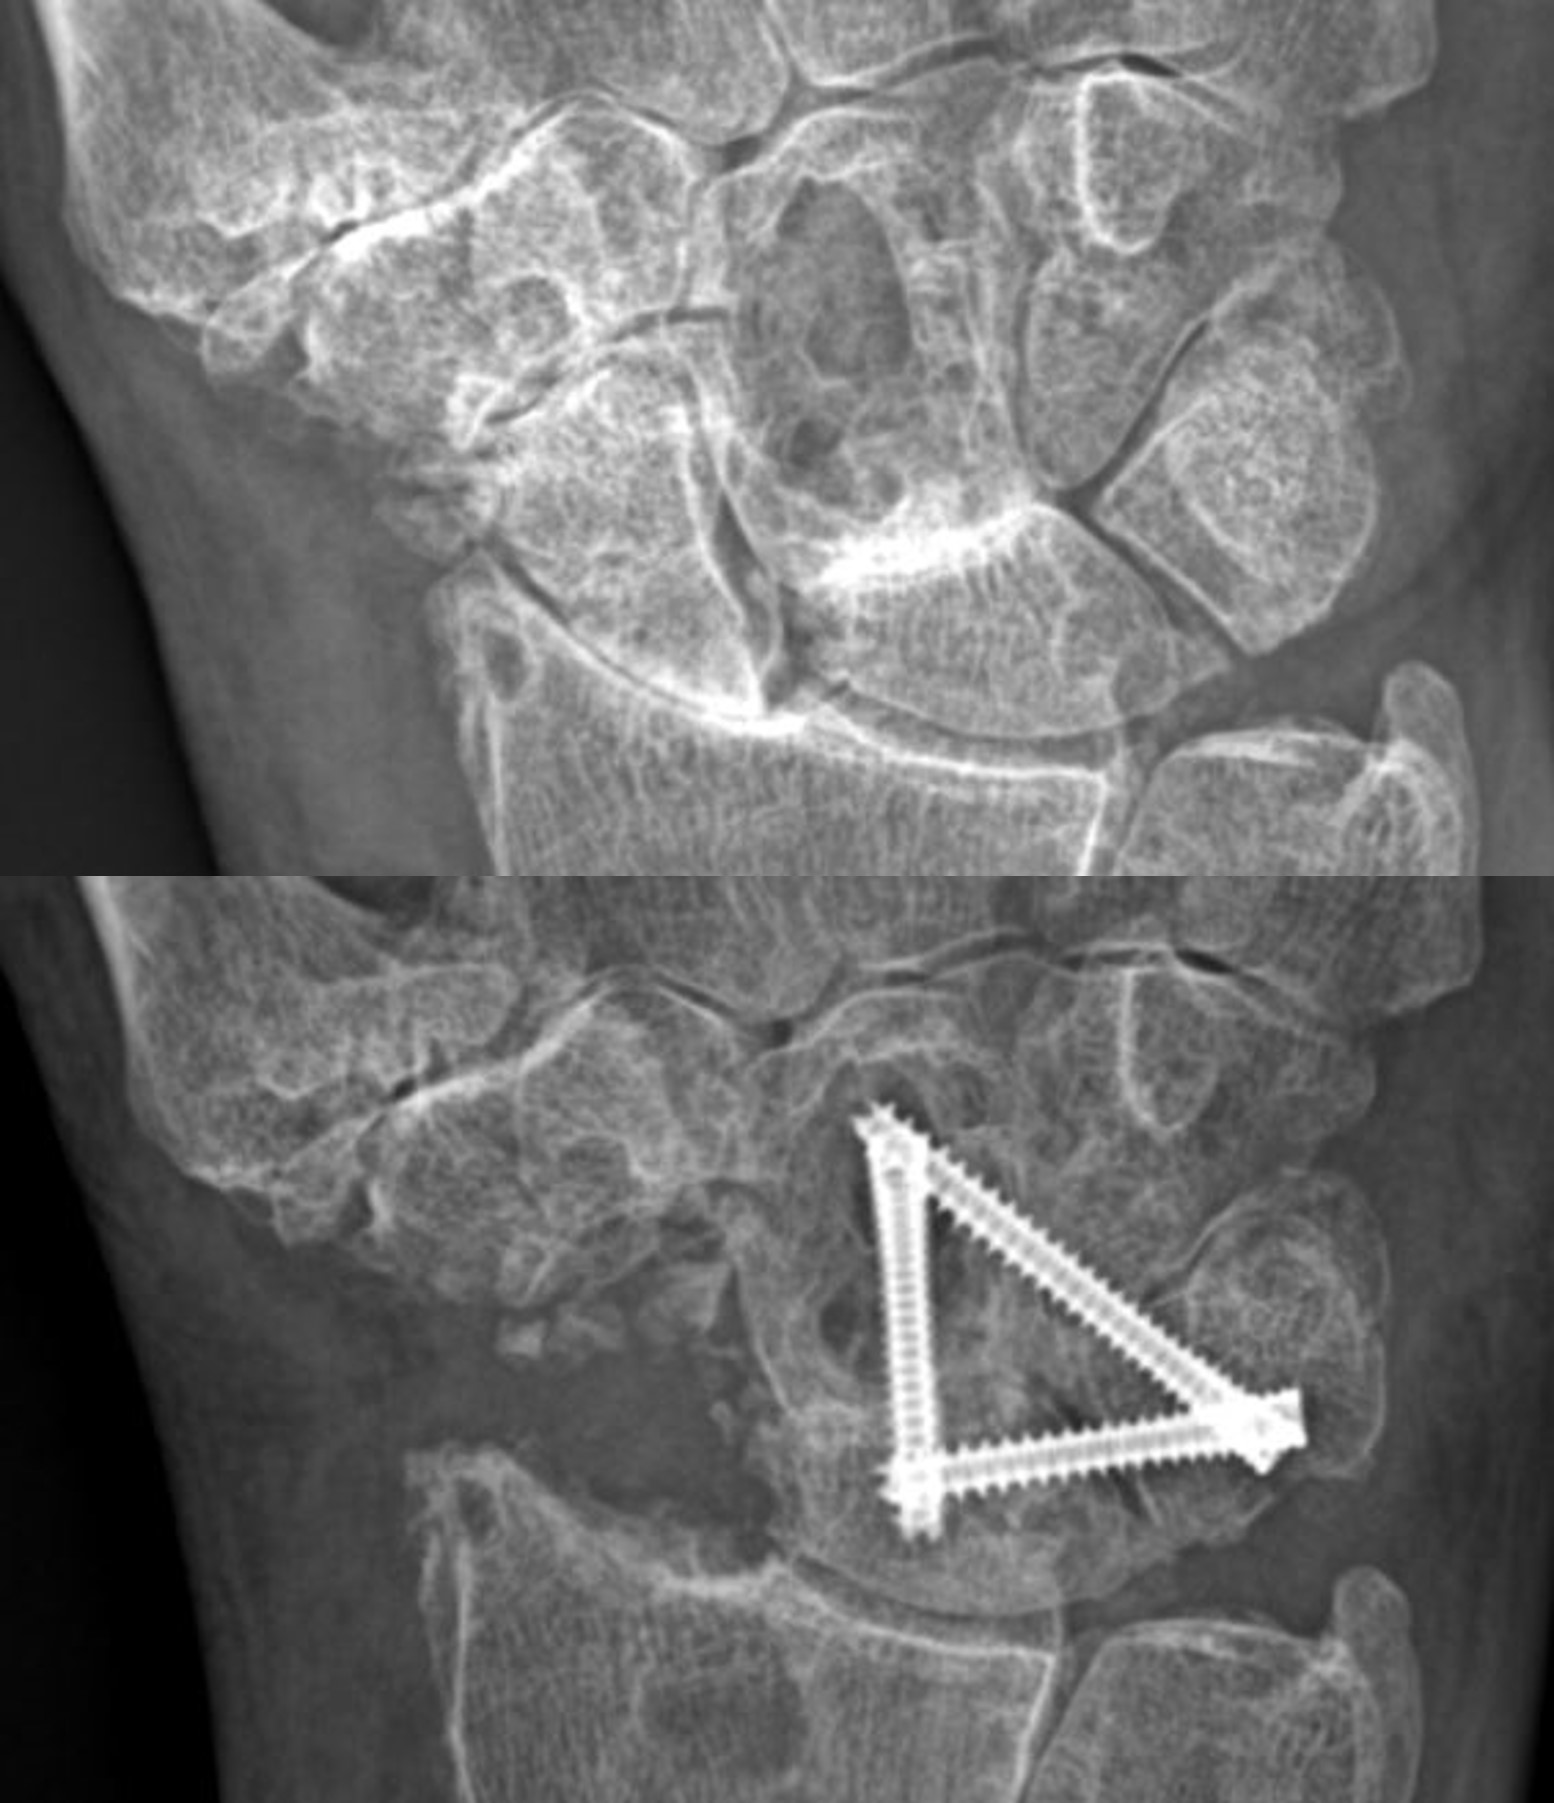

Joint Fusion

Also known as arthrodesis, joint fusion surgery uses pins, rods, or plates to join bones. This creates a single bone, dramatically reducing pain and other symptoms. Joint fusion surgery can be performed on severely arthritic joints of the fingers.